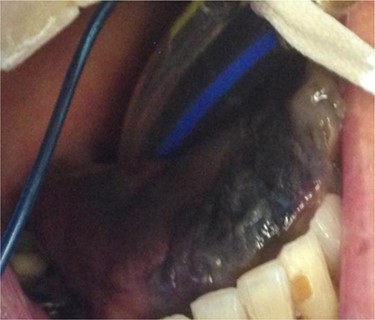

On Day 3, a black tongue was noted, and referral was made to the maxillofacial team (Fig. 1). Blackness of the left tongue dorsum was obvious. The patient was very unwell. Chlorhexidine mouth was prescribed.

At Day 34, the patient was taken back to theatre by the maxillofacial team. Much of the anterior and part of the posterior third of the dorsum of the tongue was necrotic (Fig. 2). The necrotic area was removed, and the tongue debrided to healthy tissue.